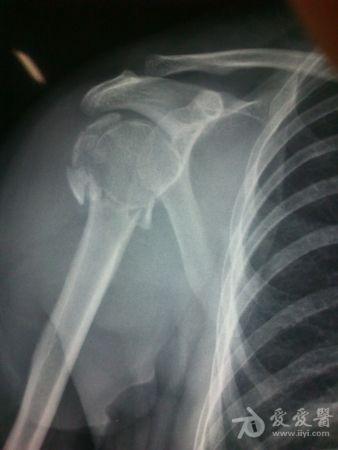

病史特点及病情摘要:1、患者女性,51岁。2、患者自诉入院前1年余因右肱骨外科颈骨折在外院行切开复位内固定术,术后右肩关节疼痛、活动受限,一直未予处理,今为明确诊治入院。患者精神、食欲、睡眠尚可。3、既往史、个人史、家族史无特殊。4、入院查体:生命征平稳,心肺腹检查未见异常,NS(-)。专科情况:右上臂近端内侧见一约15cm手术切口疤痕,愈合佳,右肩关节能外展20度,前屈、后伸及旋前、旋后功能障碍,余关节活动好。舌质红,苔薄白,脉实。5、辅助检查:右肩关节正侧位片:右肱骨外科颈骨折内固定术后再骨折伴右肩关节脱位。

诊断:右肱骨外科颈骨折内固定术后再骨折伴右肩关节脱位

我院门诊

同意楼主观点,患者第一次手术复位欠佳,但可勉强接受。但钉子穿出,是手术后肩关节疼痛的主要原因,现在看骨折已愈合,头无明显头坏死迹象,只需取出内固定,麻醉下活动肩关节,使肩关节活动度改善,术后加强功能锻炼,应该恢复不错。

是的,就这样了:帮忙取出了内固定物,病人是没有什么不满意的理由的.后期,让病人循序渐进地进行肩关节的功能锻炼,避免再次骨折,